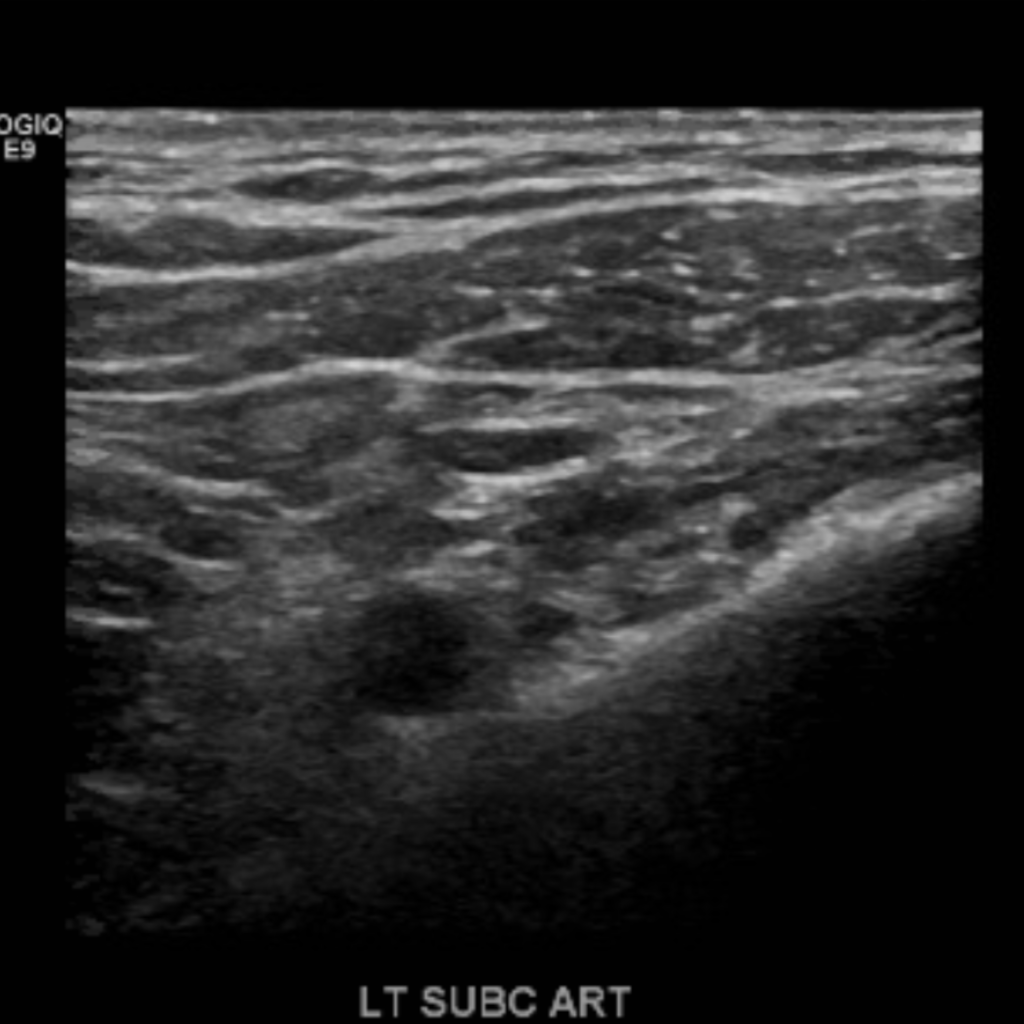

The subclavian artery arises from the brachiocephalic artery on the right and off of the aortic arch on the left. This artery further divides into the axillary, brachial, radial, ulnar, palmar and digital arteries respectively.